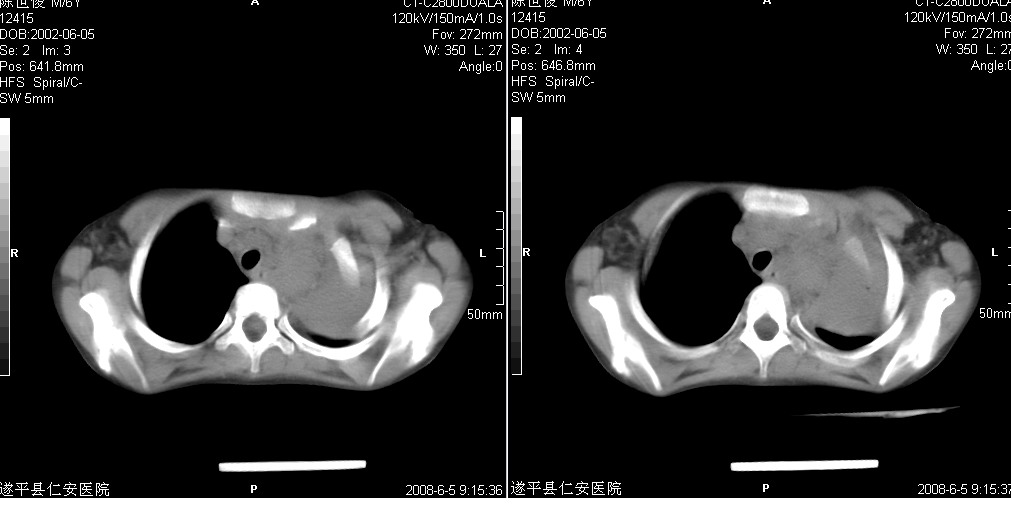

以下是引用xxhwh在2008-6-10 18:40:00的发言:[br]男,6岁,无规则发热一月余,体温在37.8——39度之间。一月前拍胸片示左上肺密度增高影,进行抗炎治疗8天,复查胸片未明显吸收。又改变抗菌素继续治疗半月,照胸片示病灶吸收不明显,行ct检查[br]征象:左上肺前段呈密实影,内可见支气管气像,远侧见絮状模糊影,中上纵隔左移。[br]意见:左上肺前段膨胀不全及感染,考虑为支气管异物或支气管内膜结核所致,[br]建议追问有无异物吸入史,行痰检及ppd检查